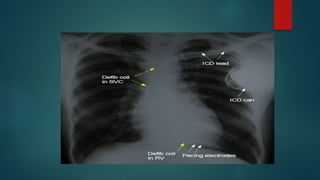

 An ICD responds to dysrhythmia by delivering an internal electrical shock

 The ICD system consists of a pulse generator and leads for dysrhythmia

 In addition to internal defibrillation, an ICD can produce anti-tachycardia

CHEST X-RAY

Lead position

Paced position

Type of CIED

 Determining that a CIED is present and defining the functionality of the

device (e.g. pacemaker or ICD).